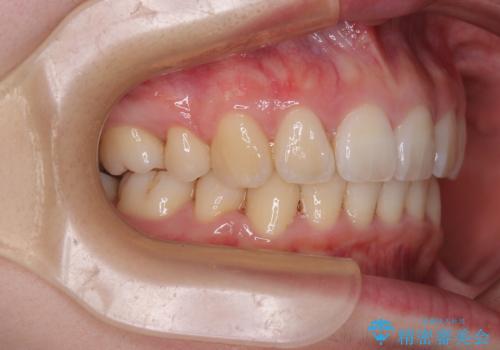

- 下唇に跡がつくほどに飛び出した上顎前歯を気にして来院された患者様です。

来院された時から4本の抜歯が必要であることを理解されていらしており、通法通り上下左右の第一小臼歯4本を抜歯し、ワイヤー装置にて矯正治療を行うこととしました。

順調に治療が進み、2年弱で想定していたとおりの仕上がりにて治療を終えることができました。